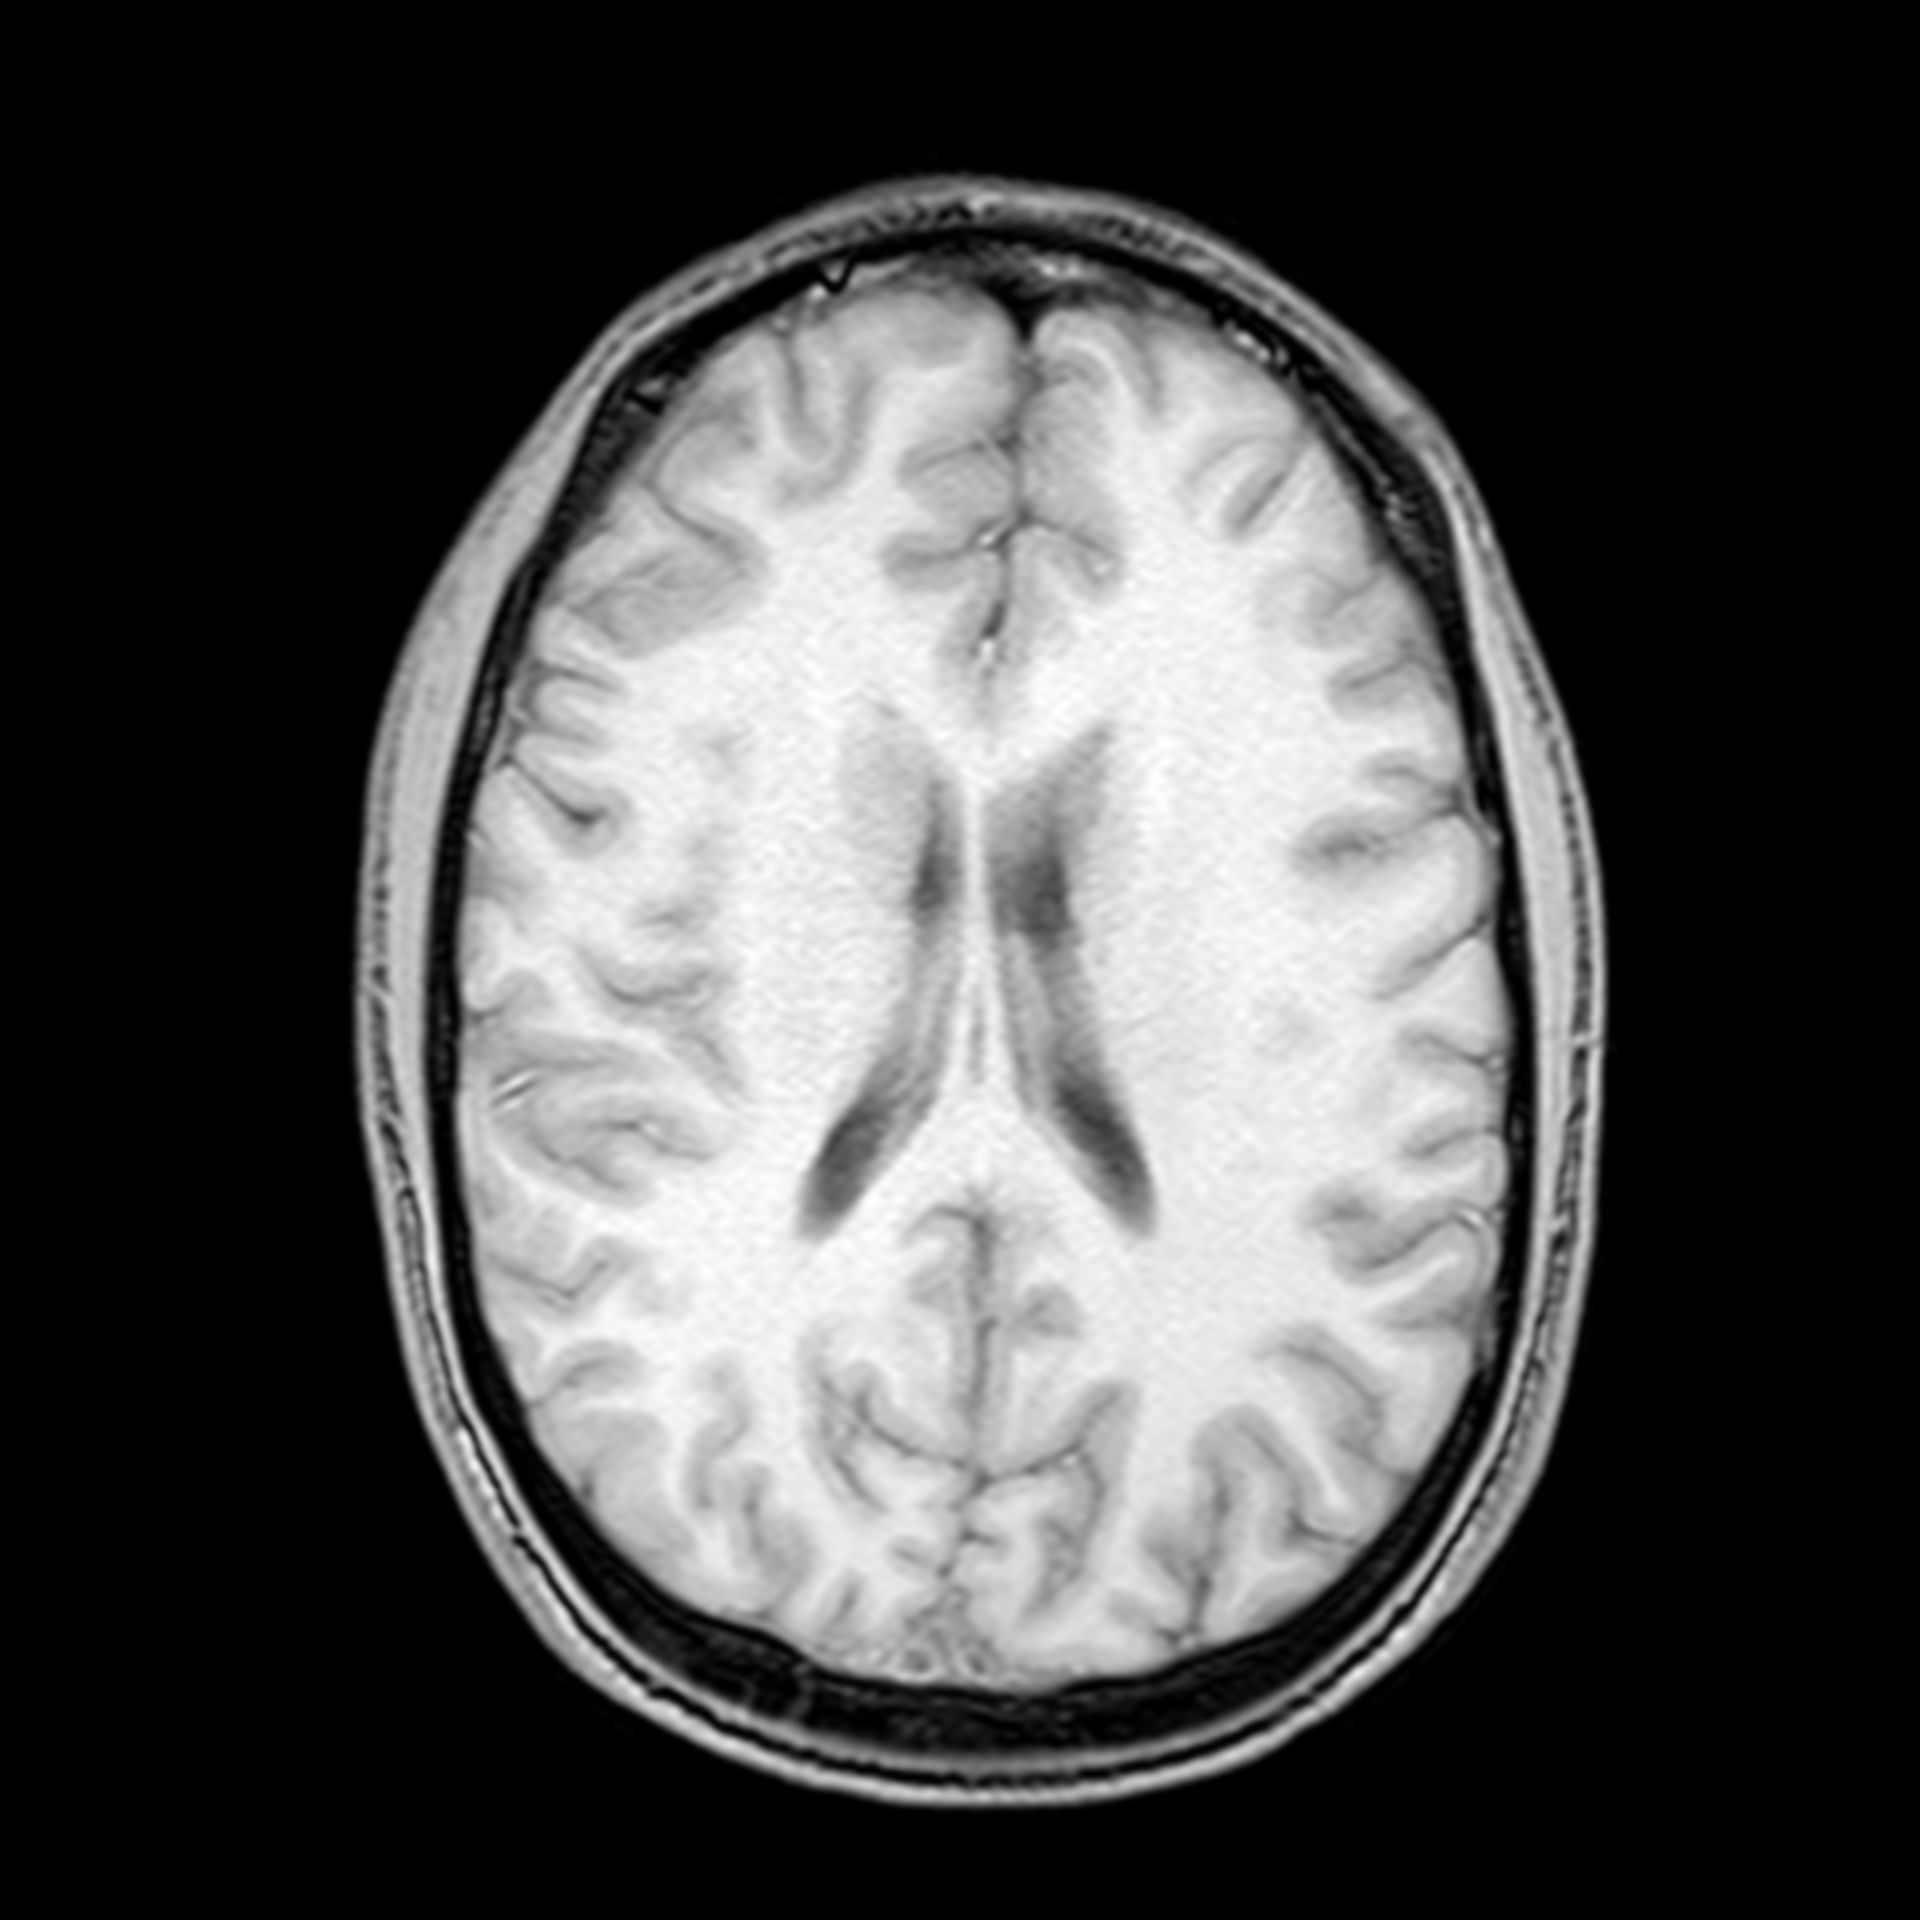

(16/26) MRT Schädel in Transversalebene, T₁‐gewichtet, FFE – DocCheck MRT Knie – DocCheck

MRT Schädel – DocCheck MRT Bild, könnte das ein Tumor sein? Kennt sich jemand damit aus? Könnte die helle Fläche ein …

MRT Schädel – DocCheck Sichere Prostatavorsorge mittels MRT-Untersuchung der Prostata

(11/26) MRT Schädel in Transversalebene, T₁‐gewichtet, FFE – DocCheck MS Herd MRT (1) – DocCheck

(16/34) MRT Schädel in Sagittalebene, T₂‐gewichtet – DocCheck MRT Bilder-Hubbel-??? Hilfe (Kopf)

MRT Schädel – DocCheck #MRT: Sungai Buloh – Kajang Line Phase 1 To Officially Start 16th December – Hype Malaysia

MRT 4 Schädel – DocCheck Taipei MRT Roadmap